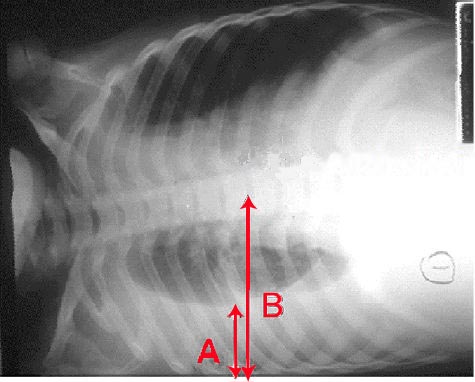

Aspiration Pneumonia

Aspiration pneumonia is seen in individuals who are at risk for aspiration, such as alcoholics and people who are unconscious.

The oropharynx’s anaerobic bacteria, such as Bacteroides, Fusobacterium, and Peptococcus, are typical causes of aspiration pneumonia.

Aspiration pneumonia classically leads to a right lower lobe abscess (due to the angle of the bronchus), but may present in different lobes.

Compared to the left, the right main stem bronchus branches anatomically at a less sharp angle.